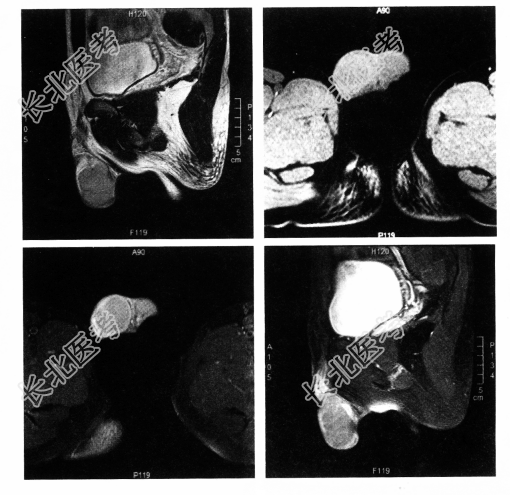

[材料题] 患者男,31岁,发现阴囊肿物伴下坠感1个月余。

多项选择题1.根据症状及MR表现分析,最可能的诊断是